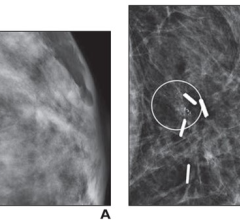

March 15, 2024 — Screening-detected radial scars without atypia at core-needle biopsy (CNB) have a low upstaging rate to ...